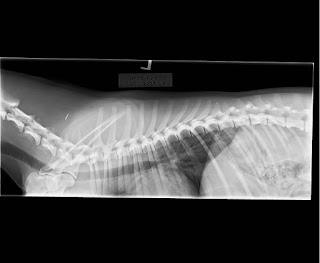

Umppa Lumppa kävi läpivalaistavana virallisesti muutama viikko sitten ja tulosten perään kyselemisen jälkeen saatiin nekin. Jos nyt ei ihan priimaa pukannut, niin en siltikään voi olla kuin tyytyväinen tähän tuontipoikaan. Lonkat olivat nipin napin B:t, juttelin niistä vielä Kennelliiton lausujan kanssa, joka hänkin sanoi että myöhemmin kuvattuna pieni löysyys voisi tiivistyä vielä A:ksi, mutta en kyllä itse näe sille tarvetta (ainakaan toistaiseksi). Lisäksi maljan reuna on hieman avoin, mikä yhdessä löysyyden kanssa tiputti A:sta B:hen. Lonkkien uudelleen kuvaukselle ei ole tarvetta myöskään siksi kun Kennelliitto hyväksyi Pevisan lievennyksen siten, ettei enää jalosteta pelkän indeksin varassa lonkkia, vaan A:t ja B:t voi risteyttää keskenään indeksistä huolimatta.

Selässä oli pieni muutos, joka ei tule Unon elämään vaikuttamaan mitenkään. Mahdollisessa jalostuskäytössä se toki tulee huomioida siten ettei nartulla ole LTV-muutosta.

Kyynärät olivat puhtaat.